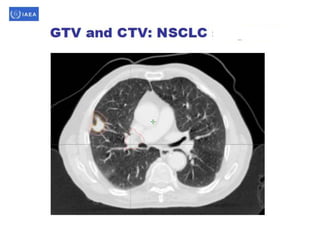

Volume definition

• Prerequisite for 3-D treatment planning.

• ICRU reports50 & 62 define & describe target

& critical structure volumes.

• volumes defined prior to treatment planning

– Gross tumor volume (GTV).

– Clinical target volume (CTV).

• Defined during the treatment planning process

– Planning target volume (PTV).

– Organs at risk.

• As a result of treatment planning, volumes described.

– Treated volume (TV).

– Irradiated volume (IRV).